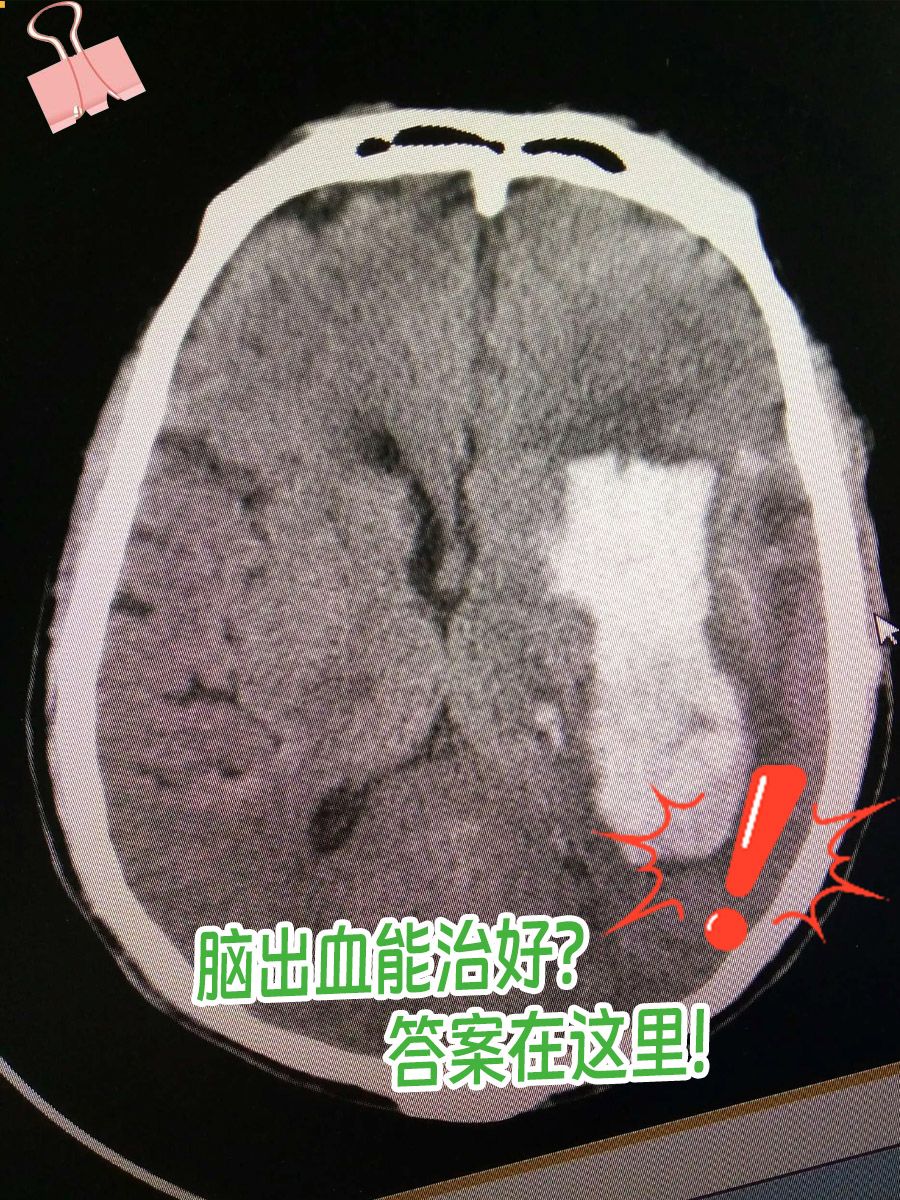

⭐脑出血能不能治好?

这与脑出血的病情严重程度有关,轻的就可以治好,重的可能就不行了。

如果脑出血的量比较大,即使通过上述药物治疗,以及必要时的手术治疗,包括开颅血肿清除术、去骨瓣减压术等,可能出的血还是会损伤和压迫周围的组织,导致偏瘫、失语等症状,后期也会留有后遗症。特别是当出血量特别大,压迫到脑干时,一般不能治好。脑干出血还可能导致脑干功能衰竭,出现呼吸心跳骤停而死亡。